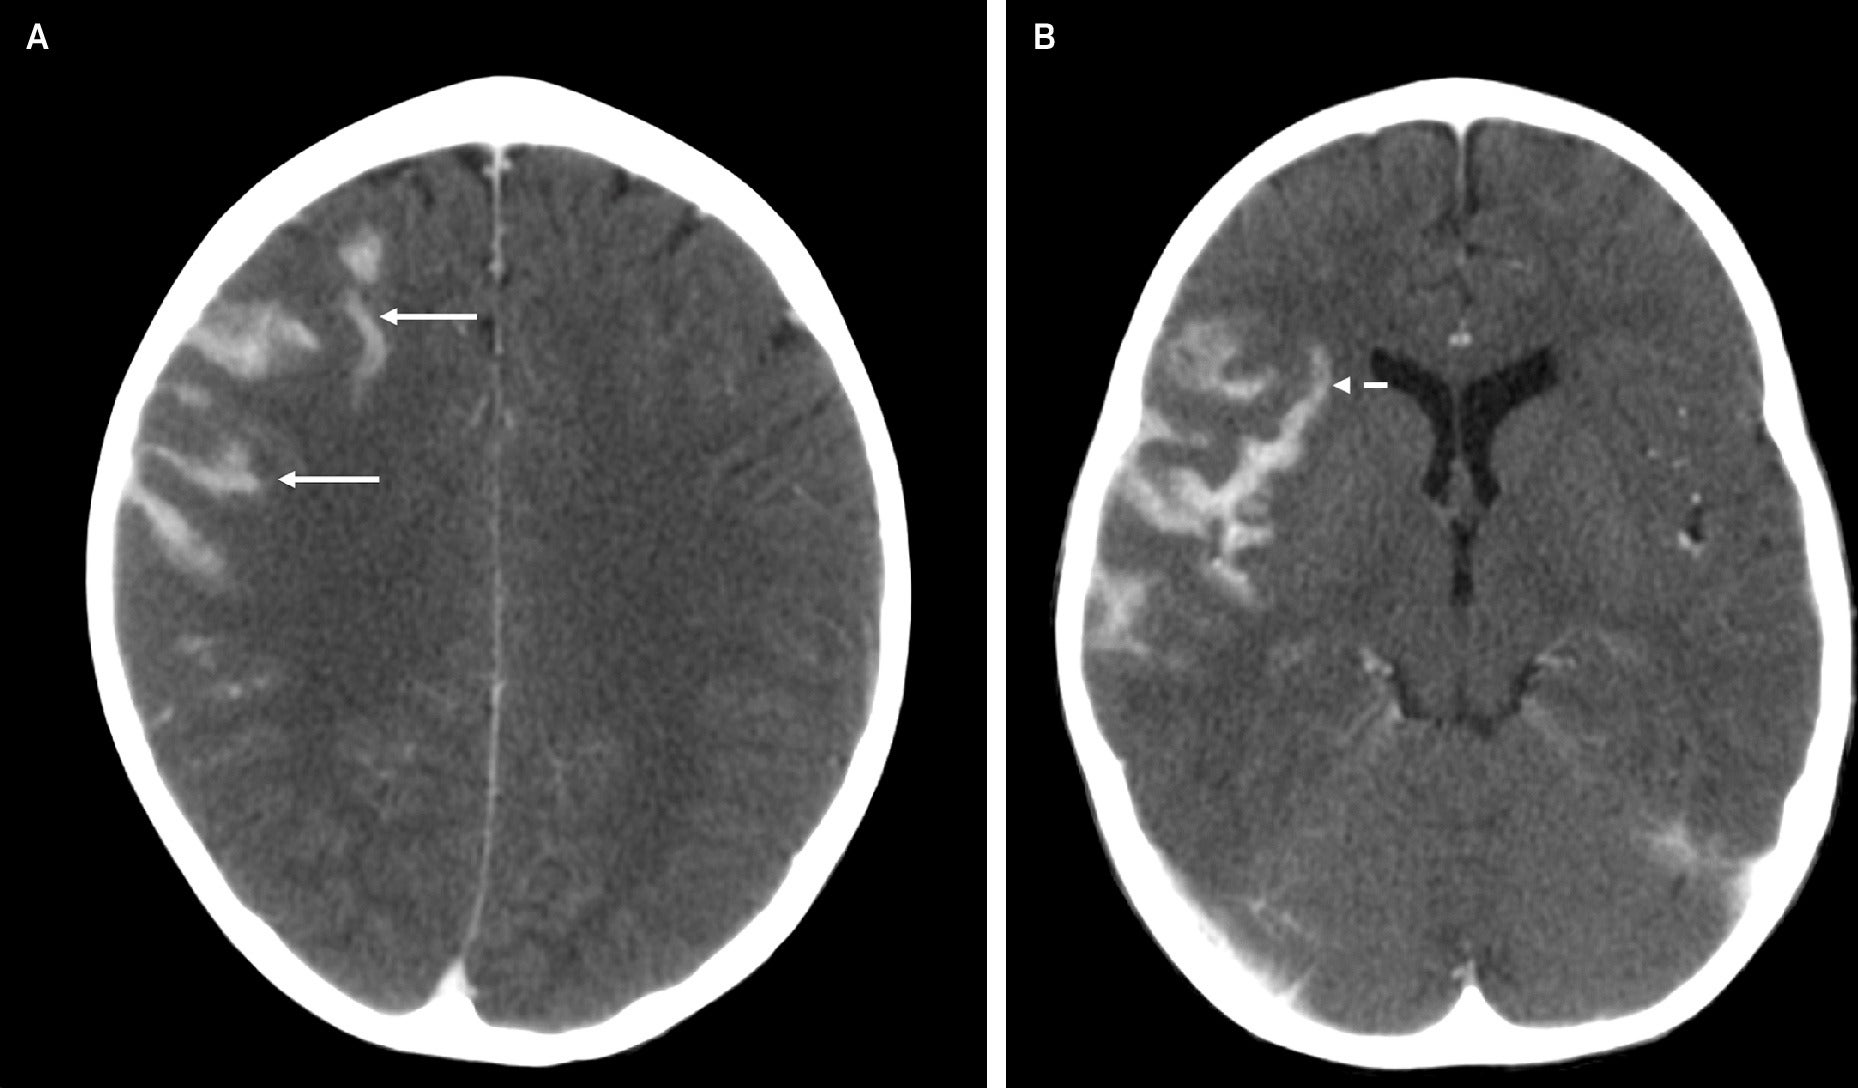

Cerebral magnetic resonance imaging (MRI) ( Figure 1 ) demonstrated signal abnormality in the Sylvian fissure along the insular cortex. No significant vasogenic edema was noted. Cranial computed tomography (CT) ( Figure 2 ) obtained 19 days later showed an interval increase in the extension of the hyperattenuating lesion in a gyriform distribution, at this time also involving the right frontal lobe, allowing for the differences in modalities between studies. A follow-up MRI obtained 7 days after the CT demonstrated a mass-like lesion with gyriform distribution, markedly increased size, and significant surrounding vasogenic edema, consistent with worsening leptomeningeal disease ( Figure 3 ).

Post-contrast axial brain CT images demonstrate new, mass-like hyperattenuation in the right frontal lobe (A, solid arrows) and more pronounced hyperattenuating lesions in the right Sylvian fissure, in a gyriform distribution along the insular cortex and frontotemporal operculum (B, arrows), compared with a brain MRI 19 days earlier.